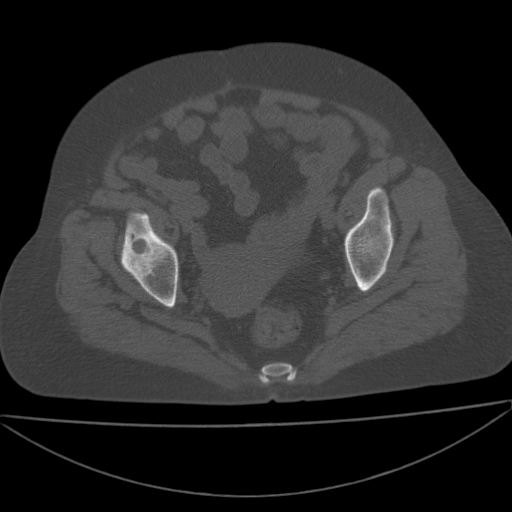

以下是引用余辉在2009-4-23 17:08:00的发言:[br]考虑右髋关节退行性变.股骨颈改变考虑陈旧性骨折可能,股骨头顶部关节面下似有透亮区,股骨头皮质环增厚,考虑有股骨头坏死

以下是引用王显瑞在2009-4-23 16:45:00的发言:[br]考虑股骨颈陈旧性骨折,股骨头缺血型坏死